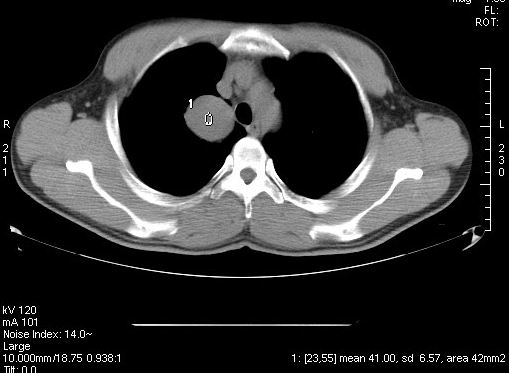

标题: CT7610:[原创]右上纵隔还是肺内占位,请会诊!

体检发现,无任何不适。

右肺见纵隔旁见类圆形界清等密度肿块影,直径约5.0cm,增强呈不均匀强化,重建的图片上看到肿块内可见强化的血管影,考虑:1,肺腺瘤;2,肺肉瘤。

肿块内可见强化的血管影,支气管囊肿不支持。